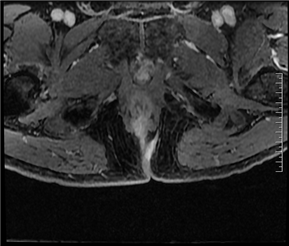

磁共振(MRI)检查的目的是为了判断内口、外口的位置、数目;瘘管走形、瘘管与括约肌复合体之间的关系;判断是否合并脓肿;寻找分支瘘管或窦道;判断活动性与非活动性,从而为临床诊断与治疗规划提供重要参考。

(MRI影像示意图,展示肛瘘常见表现)

在MRI图像中:

◆ 活动期肛瘘MR常表现为T2WI高信号,增强明显强化;

◆ 寻找内口以T1WI增强序列最佳,其次为T2WI抑脂序列,内口影像表现为括约肌内点状T2WI高信号,明显强化或括约肌受牵拉,括约肌间隙消失;

◆ 直径<1CM为瘘管,瘘道的管径最宽处直径>1CM的局限膨隆为脓肿;

◆ 肛瘘愈合期或慢性期,T2WI常表现为低信号,强化减弱或无强化。

四、MRI在肛瘘诊疗中的角色